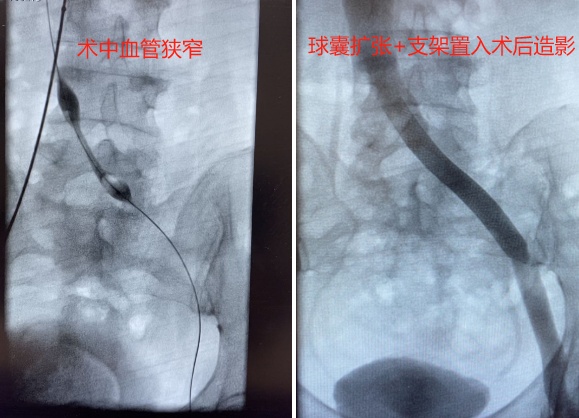

微创外一科团队医生与患者及家属充分沟通,立即行下腔静脉滤器置入术+左侧髂总静脉血栓抽吸取栓术+左侧髂总静脉狭窄球囊扩张术+左侧髂总静脉支架置入术。术后下肢肿痛缓解,患者当天下床活动,3天后顺利出院。